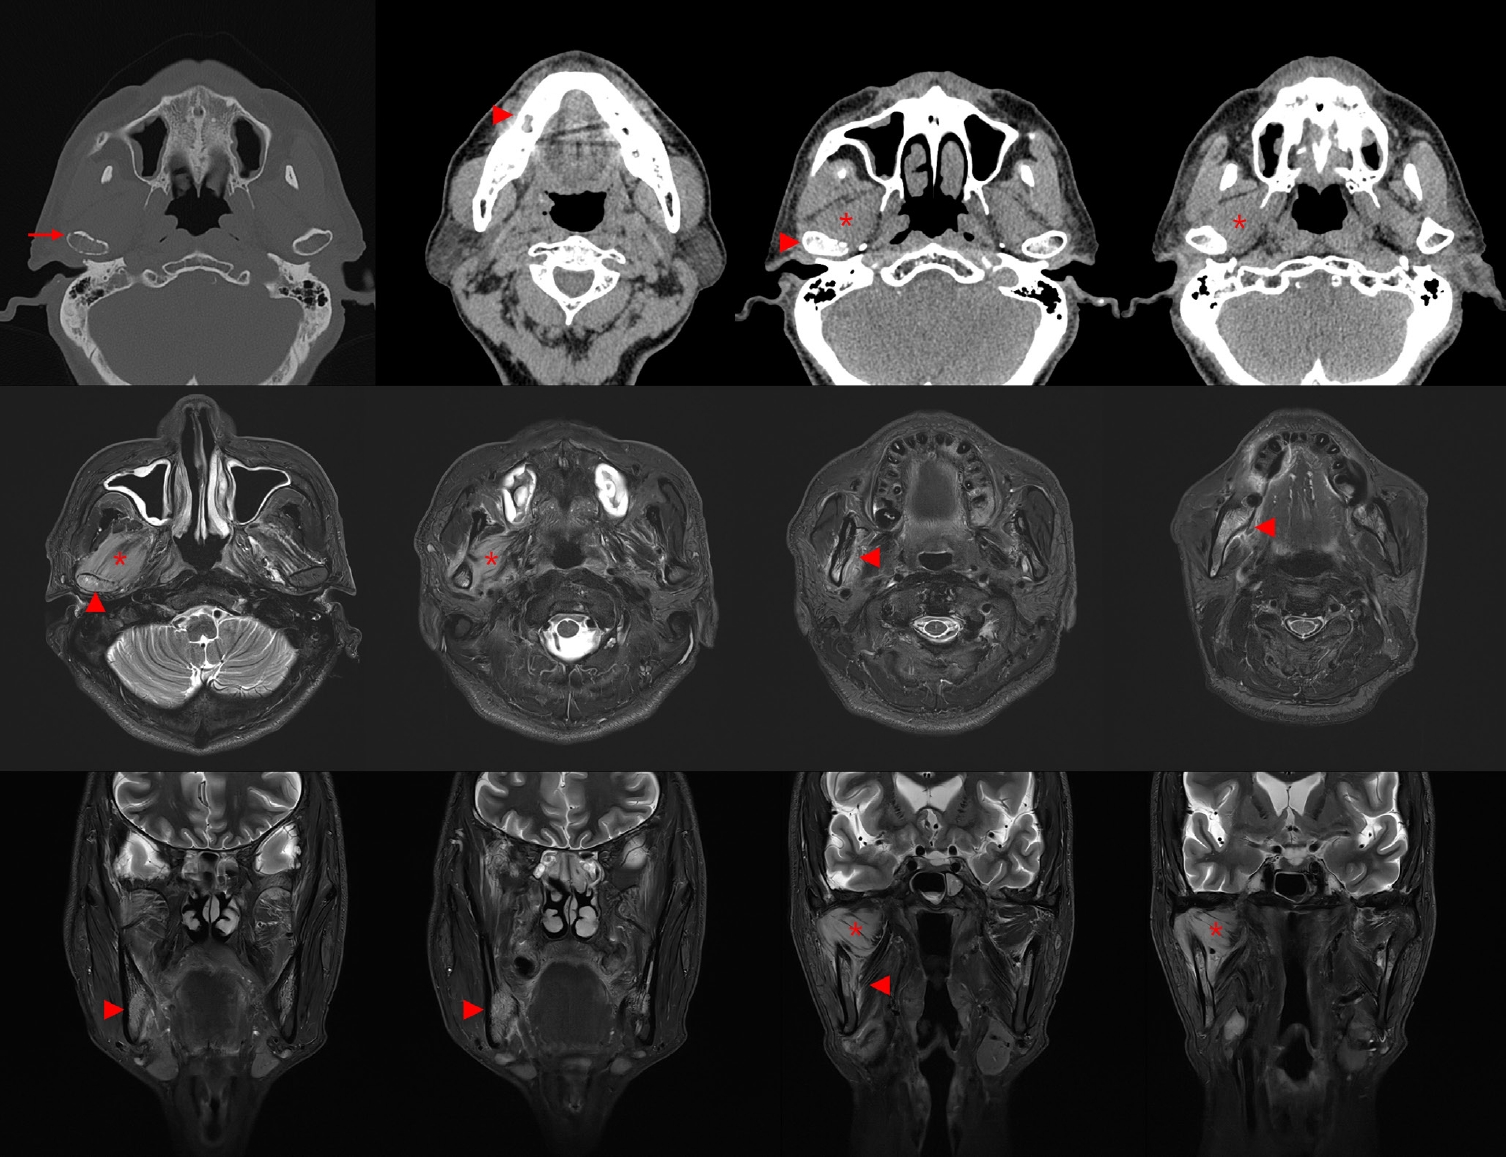

Initial panoramic view and non-contrast computed tomography (CT) of the mandible showed thickening of the lamina dura and irregular residual alveolar crest at the #46 extraction site (Fig. 1). Based on the clinical presentation and radiologic findings, the patient was diagnosed with incipient osteomyelitis of the right mandibular body, and oral antibiotic therapy was initiated.

Fig. 1.

Initial panoramic and computed tomography (CT) imaging findings of the mandible. Panoramic radiograph shows the extraction socket at the #46 site. Non-contrast axial CT image reveals thickening of the lamina dura and irregular residual alveolar crest at the right mandibular body (arrows), consistent with early-stage osteomyelitis.

Fig. 1. Initial panoramic and computed tomography (CT) imaging findings of the mandible. Panoramic radiograph shows the extraction socket at the #46 site. Non-contrast axial CT image reveals thickening of the lamina dura and irregular residual alveolar crest at the right mandibular body (arrows), consistent with early-stage osteomyelitis.